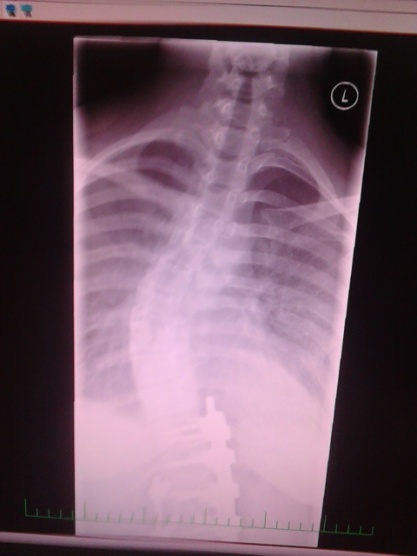

I já jsem se dozvěděla, že mě operace nemine. Ze 14st se mi to zhoršilo na 40st.

nyní mám 38° a jestli se to do září nezlepší tak pojedu na operaci do Brna

Já mam skoliozu od 10ti leteď je mi 15 let), poslali mě do ústí a tam sem měla 19 stupňů nasadily mi korzet+rehabilitace, po půl roce sem měla 14 stupňů jenže mi to zas spadlo na 22 a tak sem se držela až do deváté třídy pořád mi řikali: "kdyby ti teď bylo 16 tak už ti ten korzet sundáme".. jenže v devítce sem to už nevydržela a nosila korzet jen na noc přes školu sem ho schovávala do skříně, nedávno sem byla na kontrole mám 27 stupňů doktor se zhrozil mamka mi řekla že budu cvičit každý den 2 hodiny a korzet 24 hodin denně, korzet nosim chci cvičit ale ne až tak tolik.. :/ mam ňákou šanci že by se to do září zlepšilo alespoň na zpátky na těch 22? ideálně na míň :/ mám strach že se mi to nepodaří a budu muset na operaci, a ještě bych se chtěla zeptat.. na střední školu mam jít na uměleckou.. budou mě bolet záda když budu stát pořád u stojanu?